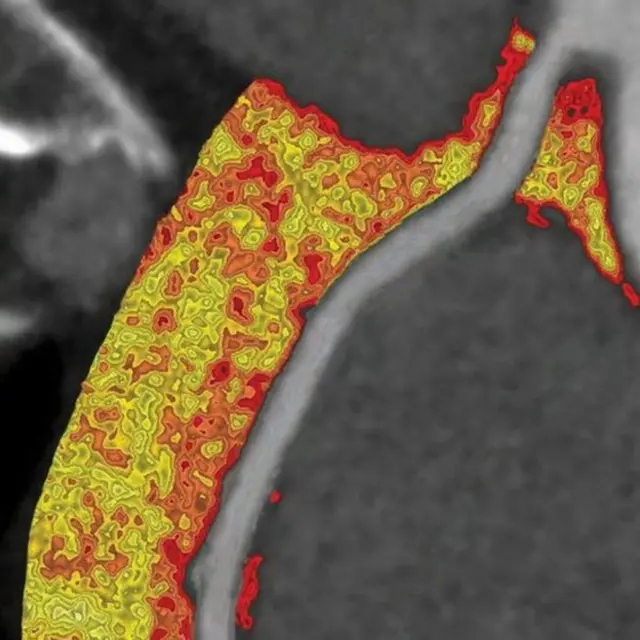

साइंस ट्रांसलेशनल मेडिसिन में छपी यह स्टडी बताती है कि खून की शिराओं के बाहर मौजूद फैट के आधार पर सूजन में बदलाव होता है.

जब सूजन बढ़ती है तो फैट टुकड़ों में बंटने लगता है और आसपास के टिश्यू ज्यादा गीले होने लगते हैं.

हार्ट से जुड़े रोगों की जांच के लिए पहले से इस्तेमाल में लाए जा रहे सीटी स्कैन के जरिए इसका भी पता लगाया जा सकता है.

कोई भी टिश्यू जितना ज़्यादा लाल होगा, सूजन का स्तर भी उतना ही बढ़ेगा और हार्ट का ख़तरा भी.

इमेज स्रोत, University of Oxford